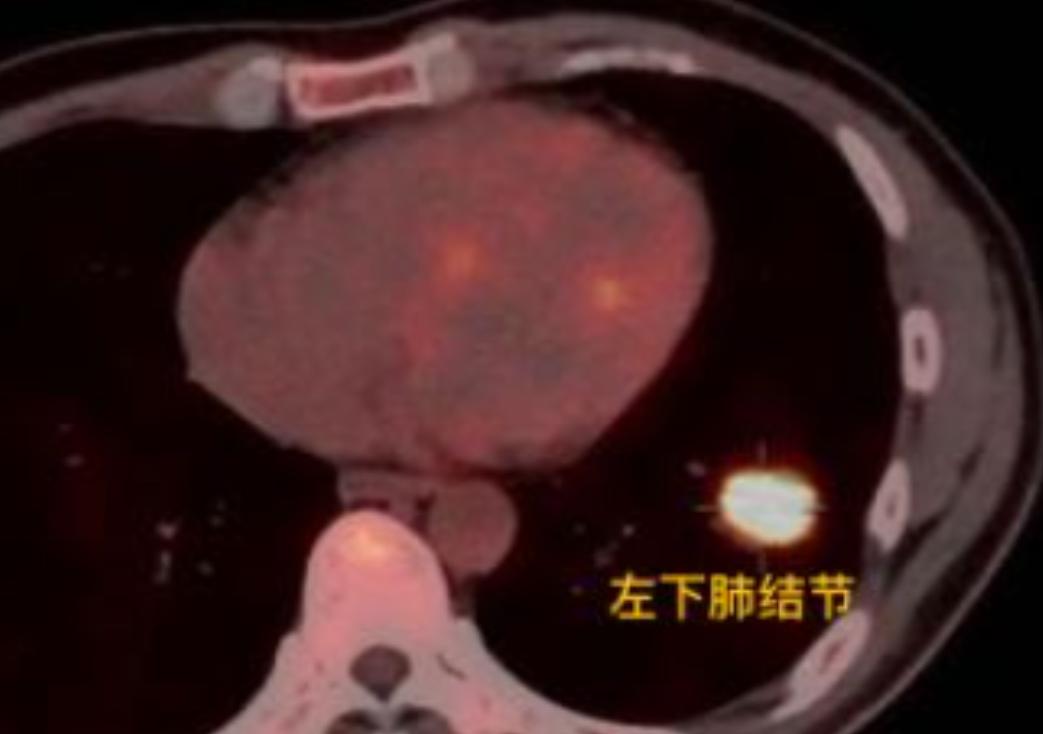

43岁的男性患者,近两年一直断断续续咳嗽,但始终没找到原因。之前做过胸片检查,结果显示“没异常”,也就没太放在心上。直到今年单位体检,做了胸部CT,才发现左下肺有个2公分的结节。 进一步做了PET-CT检查后,确认没有淋巴结和远处转移,考虑还是早期肺癌。我们通过单孔胸腔镜做了左下肺手术,很顺利,术后恢复也不错,基本能达到治愈效果。 病人当时特别不理解:为什么去年胸片什么都没发现,今年结节就长到2公分了? 我让他找出之前的胸片重新看了一遍,才发现左下肺其实早有异常,只是影像上非常模糊,不仔细看根本注意不到。 这也提醒我们,如果想排查肺内小结节或早期病变,最好直接做胸部CT。CT的分辨率更高,能清楚显示微小的病灶,而且可以细致观察结节的形态、密度和边缘特征,帮助医生判断其良恶性。 相比之下,胸片对小于1cm的结节检出率低很多。一方面是因为分辨率有限,另一方面,肺部有些位置会被肋骨、心脏等结构遮挡,特别是靠近脊柱或膈肌的深部小结节,胸片很容易漏掉,也很难准确判断性质。 所以,如果有长期咳嗽或者属于肺癌高风险人群,建议首选低剂量胸部CT筛查,更稳妥也更放心。[谢谢][玫瑰]胸外科乔贵宾医生肺结节[超话]